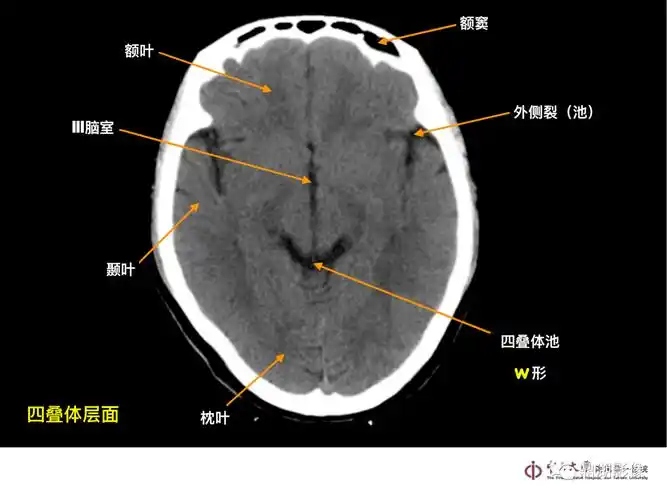

头颅ct解剖与常见出血梗死判读

一套非常牛的「头颅ct解剖图谱」

影像医生必须掌握的头颅ct解剖与常见出血梗死判读